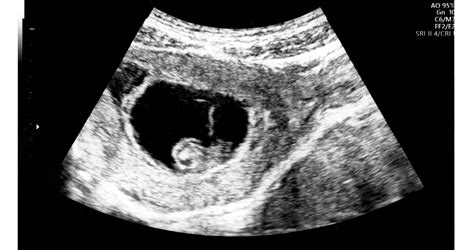

Ultrahangszűrések

- Első ultrahangszűrés: 12-13. terhességi hét

- Második ultrahangszűrés: a terhesség 19-20. hete

- Harmadik ultrahangszűrés: 30-32. terhességi hét

További javasolt ultrahangos vizsgálatokról tájékozódjon a Szent Margit Magzati Diagnosztikai Központ honlapján!